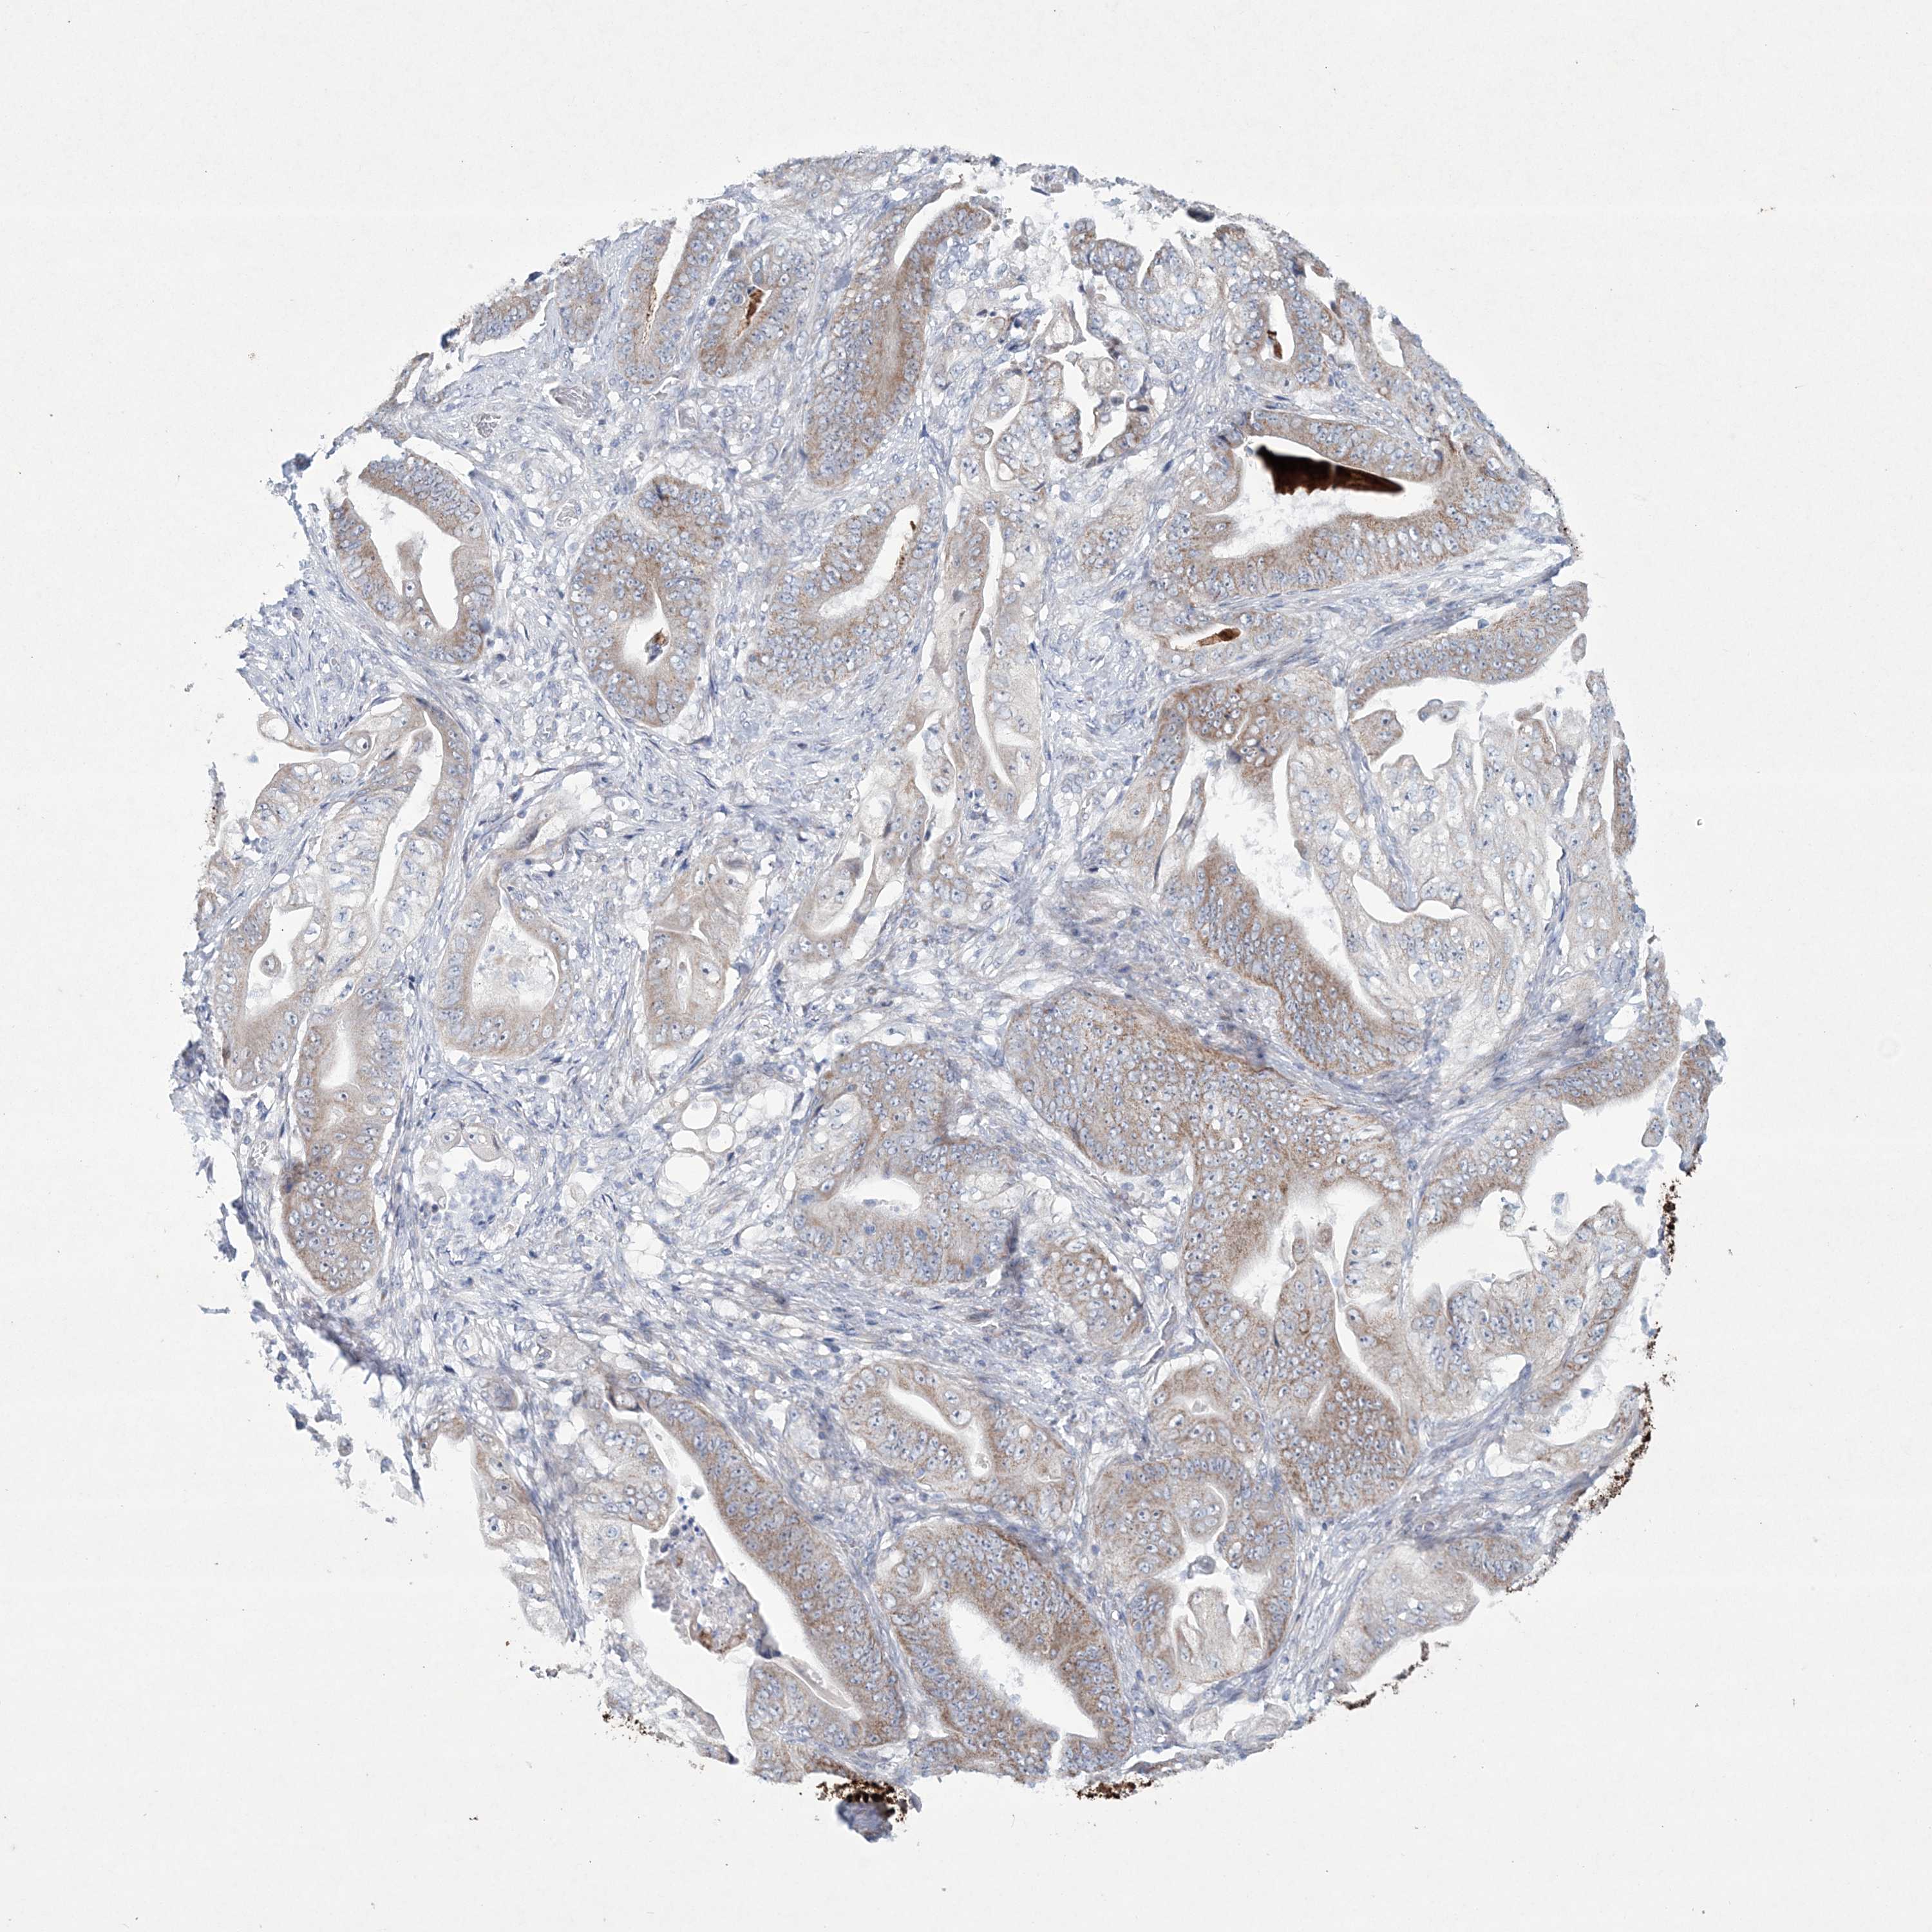

STOMACH CANCER - Protein expressioni

A mouse-over function shows sample information and annotation data. Click on an image to view it in a full screen mode. Samples can be filtered based on level of antibody staining by selecting one or several of the following categories: high, medium, low and not detected. The assay and annotation is described here.

Note that samples used for immunohistochemistry by the Human Protein Atlas do not correspond to samples in the TCGA dataset.

Antibody stainingi

Antibody staining in the annotated cell types in the current human tissue is reported as not detected, low, medium, or high, based on conventional immunohistochemistry profiling in selected tissues. This score is based on the combination of the staining intensity and fraction of stained cells.

Each image is clickable and will lead to virtual microscopy that enables deeper exploration of all samples and also displays staining intensity scores, fraction scores and subcellular localization as well as patient and tissue information for each sample.

Antibody HPA035701

Staining

High

Medium

Low

Not detected

Intensity

Strong

Moderate

Weak

Negative

Quantity

>75%

75%-25%

<25%

None

Location

Nuclear

Cytoplasmic/membranous

Cytoplasmic/membranous,nuclear

Adenocarcinoma, NOS